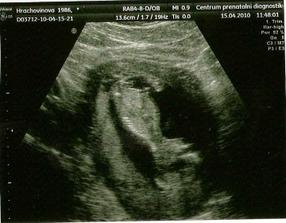

30.3.2010 Takže máme krásnou průkazku 🙂 pan doktor dělal UTZ, miminko krásně roste, odpovídáme přesně 10+5. Od hlavičky po zadeček máme už téměř 4 cm. Brali mi snad hektolitry krve ☹ Další kontrola bude už v centru prenatální diagnostiky. Tiše doufám, že nám řeknou pohlaví miminka.

15.4.2010 Vyšetření NT máme za sebou. Chvílemi to bylo docela komické. Miminko se rozhodlo, že bude dělat stojky a tato pozice se mu asi hodně líbila. Ne tak panu doktorovi, který ho nemohl pořádně vyšetřit. Proto musíme na kontrolu ještě za 3 týdny. Jinak to vypadá na chlapečka, ale ještě není nic na 100%